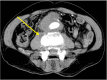

Methods: We retrospectively reviewed the database of patients who underwent OSC after EVAR from 2005 to 2018 in a single institution. Twenty-six OSCs were performed in 24 patients (median age, 74.5 years; 79.2% of males) who had undergone standard EVAR. We investigated pre-, intra-, and postoperative computed tomography or angiographic images and outcomes of the OSCs.

Results: Two main indications for OSC were persistent endoleak (50.0%) and endograft infection (EI) (38.5%). All 13 patients who underwent OSC due to endoleaks received EVAR outside of indications for use. Among 10 patients who underwent OSC due to EI, we found overlooked infection sources in 7 (70.0%) at the time of EVAR or during the surveillance period. OSC was performed at a median of 31.8 months (interquartile range, 9.4-69.8) after EVAR as an emergency (15.4%) or elective (84.6%) surgery. Aortic endograft was removed in 84.6% of cases (totally, 57.7%; partially, 26.9%), whereas it was preserved in 4 cases (15.4%). After 26 OSCs, 2 early deaths (7.7%) and 2 aortoenteric fistulae (7.7%) developed as major complications.